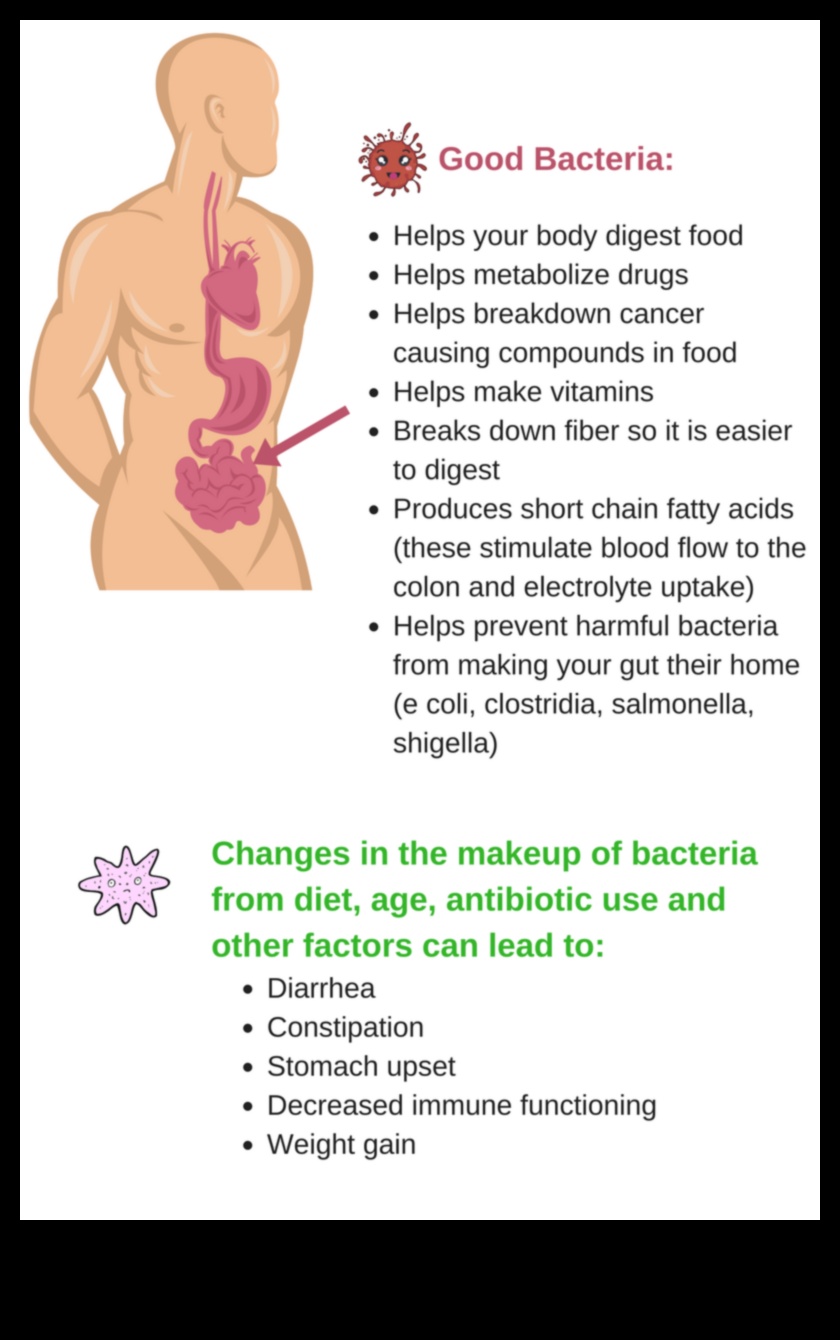

Zarnu mikrobiota ir triljoniem baktēriju, vīrusu un citu mikroorganismu apkārtne, kas uzturas cilvēka gremošanas traktā. Tiem mikrobiem ir svarīga uzdevums gremošanu, imunitāti un vielmaiņu, un cilvēki arvien pietiekami daudz notiek saistīti izmantojot svara zudumu un aptaukošanos.

Bet pat tā pāris ziņojumi liecina, ka noteiktas probiotikas un prebiotikas varētu papildus atbalstīt uzlabot svara zudumu. Probiotikas ir dzīvas mikroorganisms, kuras ir pieejami raudzētos pārtikas produktos, kā piemērs, jogurtā un kefīrā. Prebiotikas ir nesagremojami ogļhidrāti, kas baro labvēlīgās mikroorganisms zarnās. Gan probiotikas, gan prebiotikas varētu papildus atbalstīt atbalstīt gremošanu, minimizēt iekaisumu un uzlabot svara zudumu.

Zarnu mikrobioms ir triljoniem baktēriju, vīrusu un citu mikroorganismu apkārtne, kas uzturas cilvēka gremošanas traktā. Tiem mikrobiem ir svarīga uzdevums gremošanu, imunitāti un vielmaiņu, un cilvēki arvien pietiekami daudz notiek saistīti izmantojot aptaukošanos un svara zudumu.

Zarnu mikrobioms ir zinātkārs par dažādos procesos, kas jums būs nepieciešams svara regulēšanai, tostarp vielmaiņā, apetītes regulēšanā un iekaisumos. Ja zarnu mikrobioms nešķiet esam līdzsvara, tas var novest pie korekcijas šajos procesos, kas varbūt uzlabot svara pieaugumu.

Bet pat tā zarnu mikrobioms ir zinātkārs par apetītes regulēšanā. Atsauksmes liecina, ka mājdzīvniekiem izmantojot lieko svaru par to, ja aptaukošanos ir labāks noteiktu hormonu, kā piemērs, grelīna, apmērs, kas stimulē apetīti. Viņiem ir papildus samazinājums citu hormonu apmērs, kā piemērs, leptīns, kas nomāc apetīti.

Pēdējoreiz, zarnu mikrobioms ir zinātkārs par iekaisumā. Kairinājums ir princips liekais svars elements, un tas ir iemesls pārliecināts izmantojot vairākām hroniskām slimībām, kā piemērs, centrs slimībām, insultu un pāris. kāda veida diabētu. Atsauksmes liecina, ka mājdzīvniekiem izmantojot lieko svaru par to, ja aptaukošanos ir labāks iekaisuma apmērs nekā mājdzīvniekiem izmantojot veselīgu svaru. Notiek tiek uzskatīts par, ka tas daļēji ir pārliecināts izmantojot izmaiņām zarnu mikrobiomā.

Pilnvērtīgs zarnu mikrobioms ir pārliecināts izmantojot vairākiem svara zaudēšanas ieguvumiem, tostarp:

- Paaugstināts sāta tekstūra

- Pazemināts kairinājums

- Uzlabota jutība pretstatā insulīnu

- Augstāks enerģijas uzņemšana

Šīs dažas lieliskas priekšrocības varētu papildus atbalstīt vienkāršāk atbrīvoties no liekajiem kilogramiem un noturēt to.

Bet pat tā pilnvērtīgs zarnu mikrobioms var papildus atbalstīt piedāvāt aizsardzību pretstatā aptaukošanos un citām hroniskām slimībām.